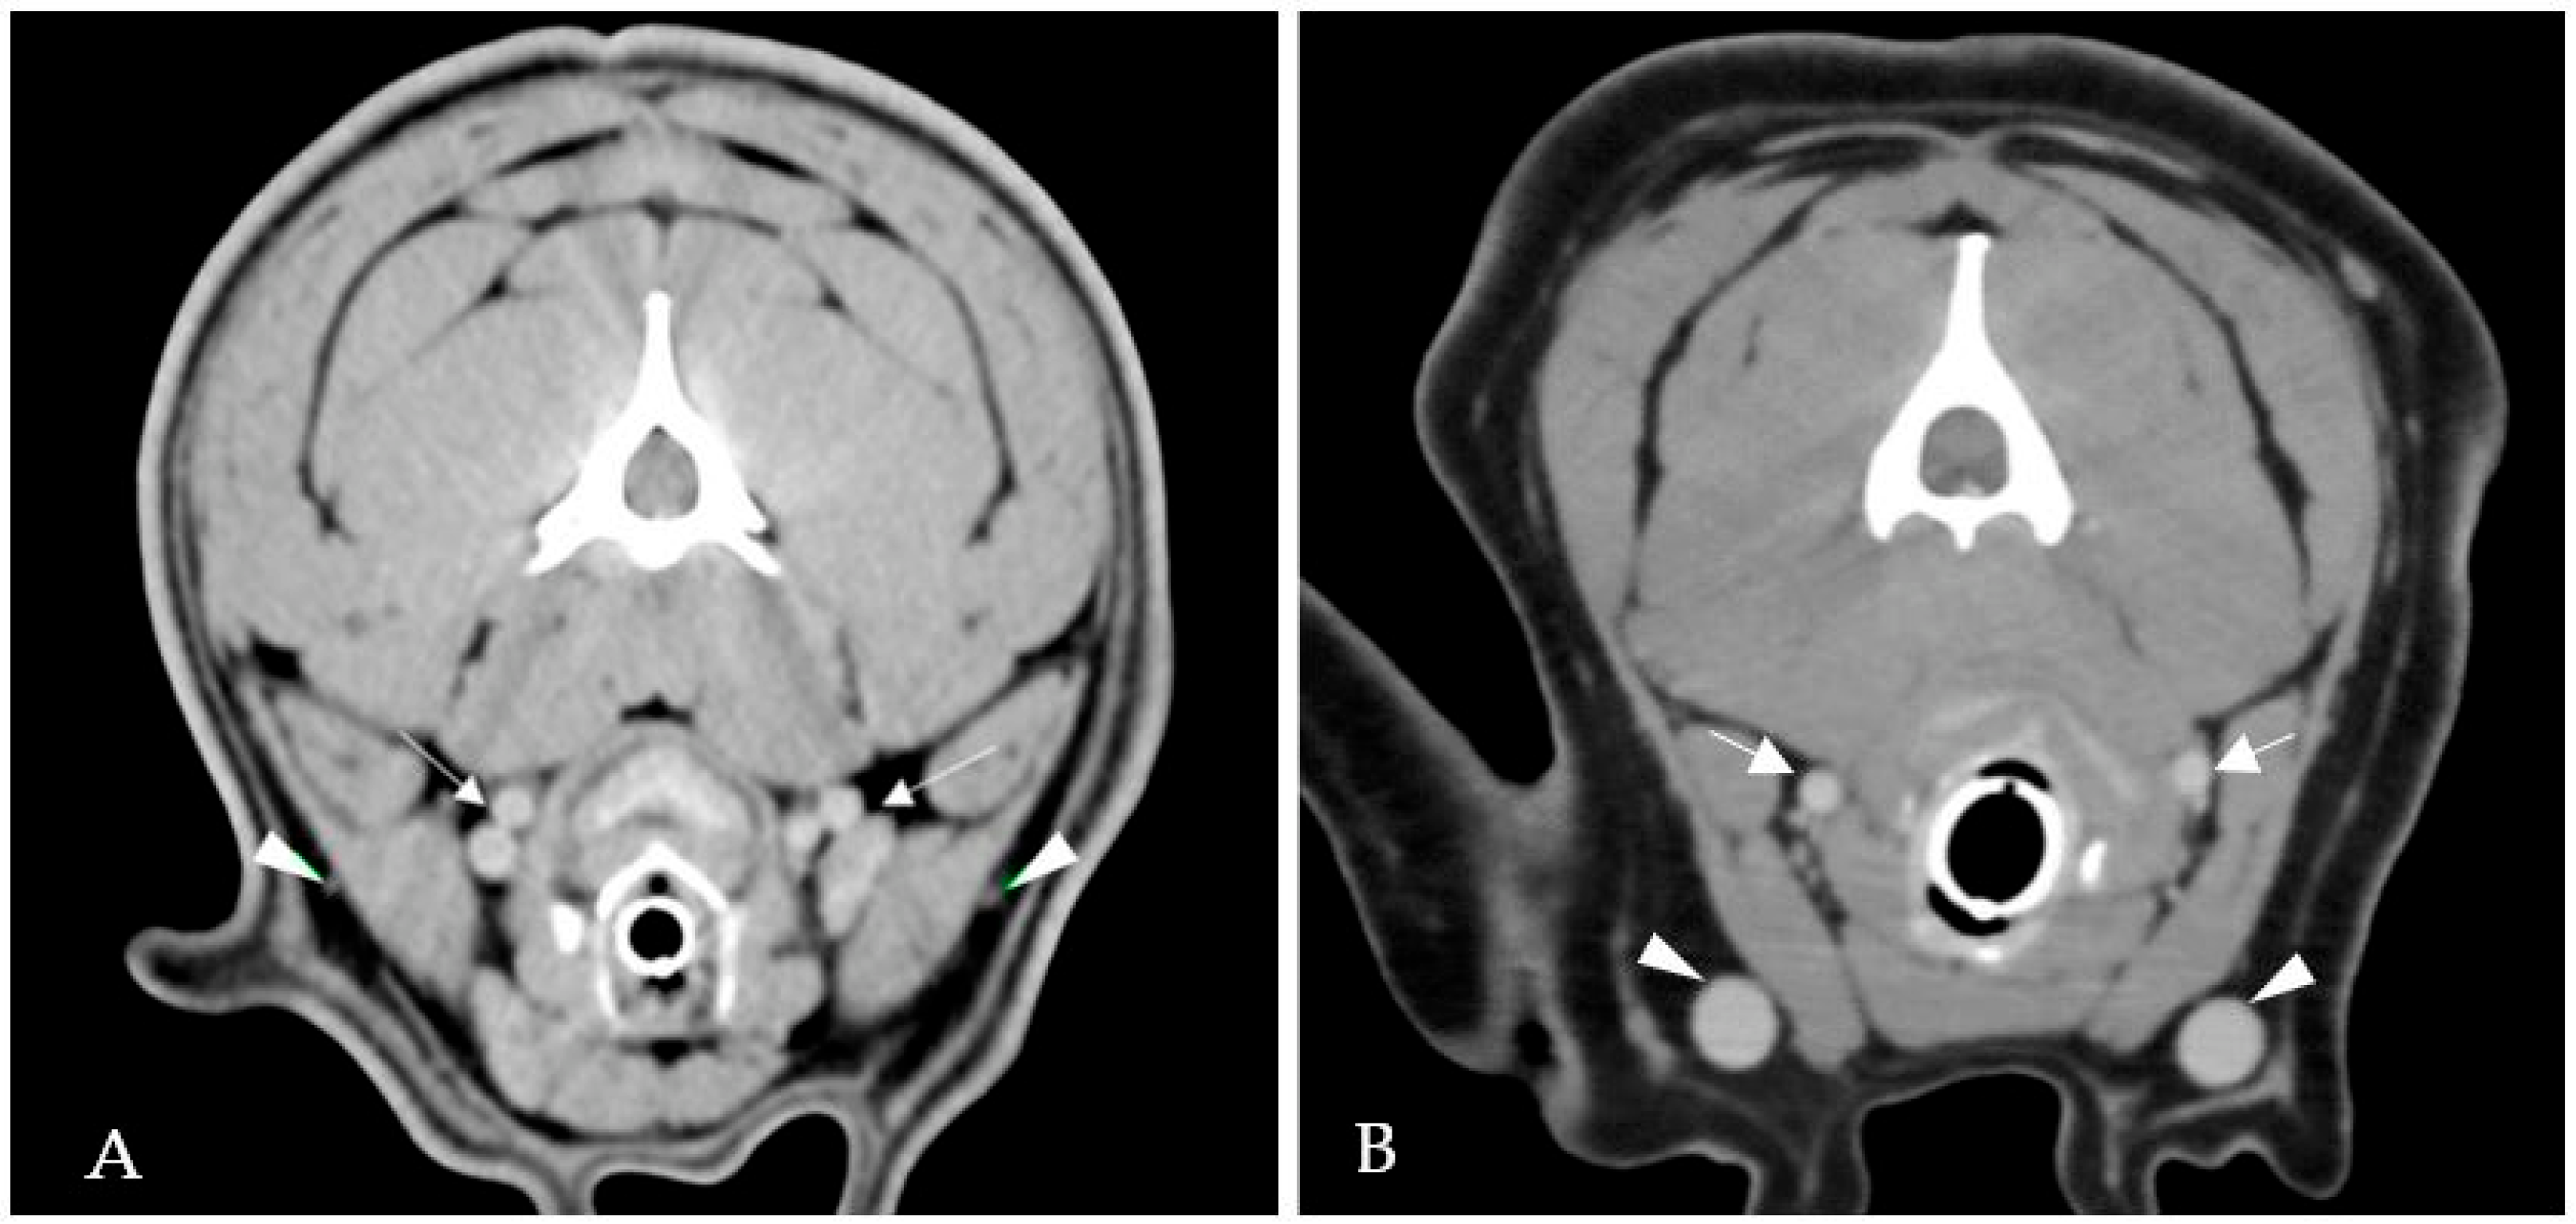

2.1. Case 1

2.2. Case 2

2.3. Case 3